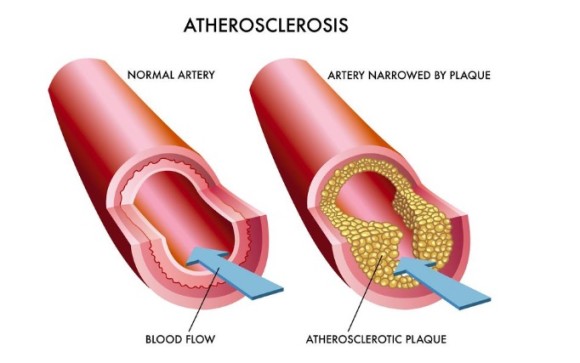

고혈압이 발생하는 이유는 여러 가지가 있지만 동맥경화(혈관이 좁아지는 현상)를 동반하면 뇌경색, 뇌졸중이 발생해 몸에 마비까지 오고 심하면 죽을 수도 있다고 한다.

동맥경화(혈관막힘)

또 이런 고혈압은 결국 혈액을 전신으로 보내는 심장에 많은 부하를 줘 심부전증이 발현될 수 있다는 것.

심부전증은 심장이 너무 고생해서그 기능을 상실함을 뜻한다.

남성의 자존심인 경직도나 크기의 크기는 결국 혈액이 얼마나 신속하고 과감하게 유입되느냐가 생명인데 고혈압은 혈액순환을 압박해 원활한 혈액흐름을 방해하게 되고 이것이 원인이 된다는 것이다.

혈액 순환 고혈압